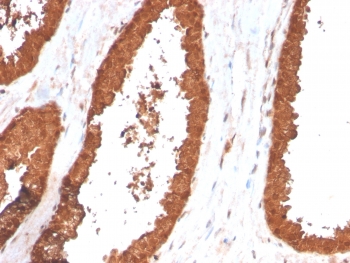

IHC staining of FFPE human prostate carcinoma with TIGIT antibody (clone TIGIT/3017). HIER: boil tissue sections in pH6, 10mM citrate buffer, for 10-20 min and allow to cool before testing.